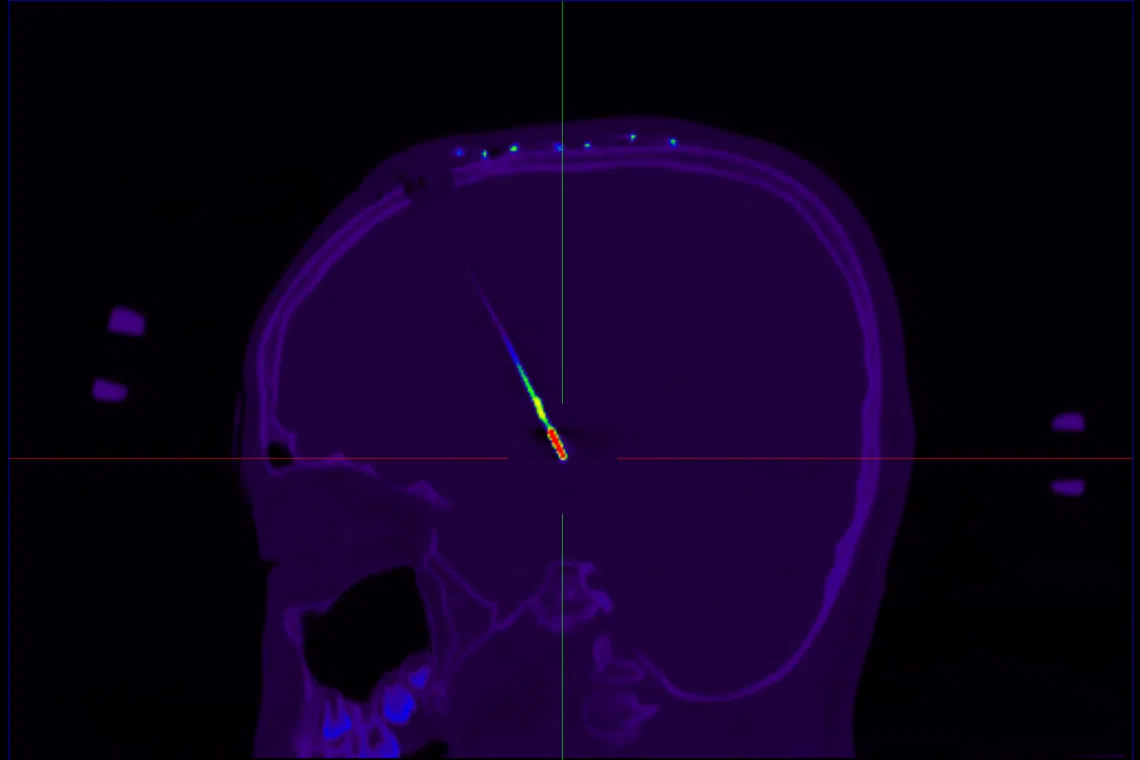

The side view of Adrian’s head, showing a DBS electrode implanted deep in the brain.

PHOTO: DR NICOLAS KON

“Two electrodes, guided by CT scans and MRI to pinpoint the exact location, were inserted 7cm into the specific areas of his brain. We had to put in two electrodes as both sides of the brain were affected,” said Dr Kon. “We were worried at the same time because Adrian was on several medications to manage his refractory dystonia and movement disorder.”

Adrian then had a CT scan and the images were combined with the MRI scans taken before surgery, creating a digital model of the brain.

Using this model, the exact location to place the DBS wire was finalised.

In the days after the surgery, the child underwent a CT scan to check if the DBS system was intact and in the correct location.